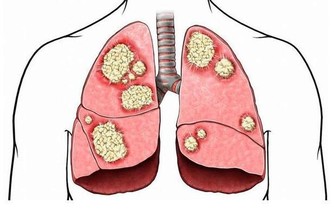

五、不要總生氣

我們總說“氣大傷肝”,其實生氣不僅傷肝,對我們整個身體都不好,這些生氣因子慢慢就會變成致病的有害因子。除了別生氣外,也不能總是愁眉苦臉的,給自己太多負面情緒,很容易衰老的。建議中年人多多開心,學會排憂解難。